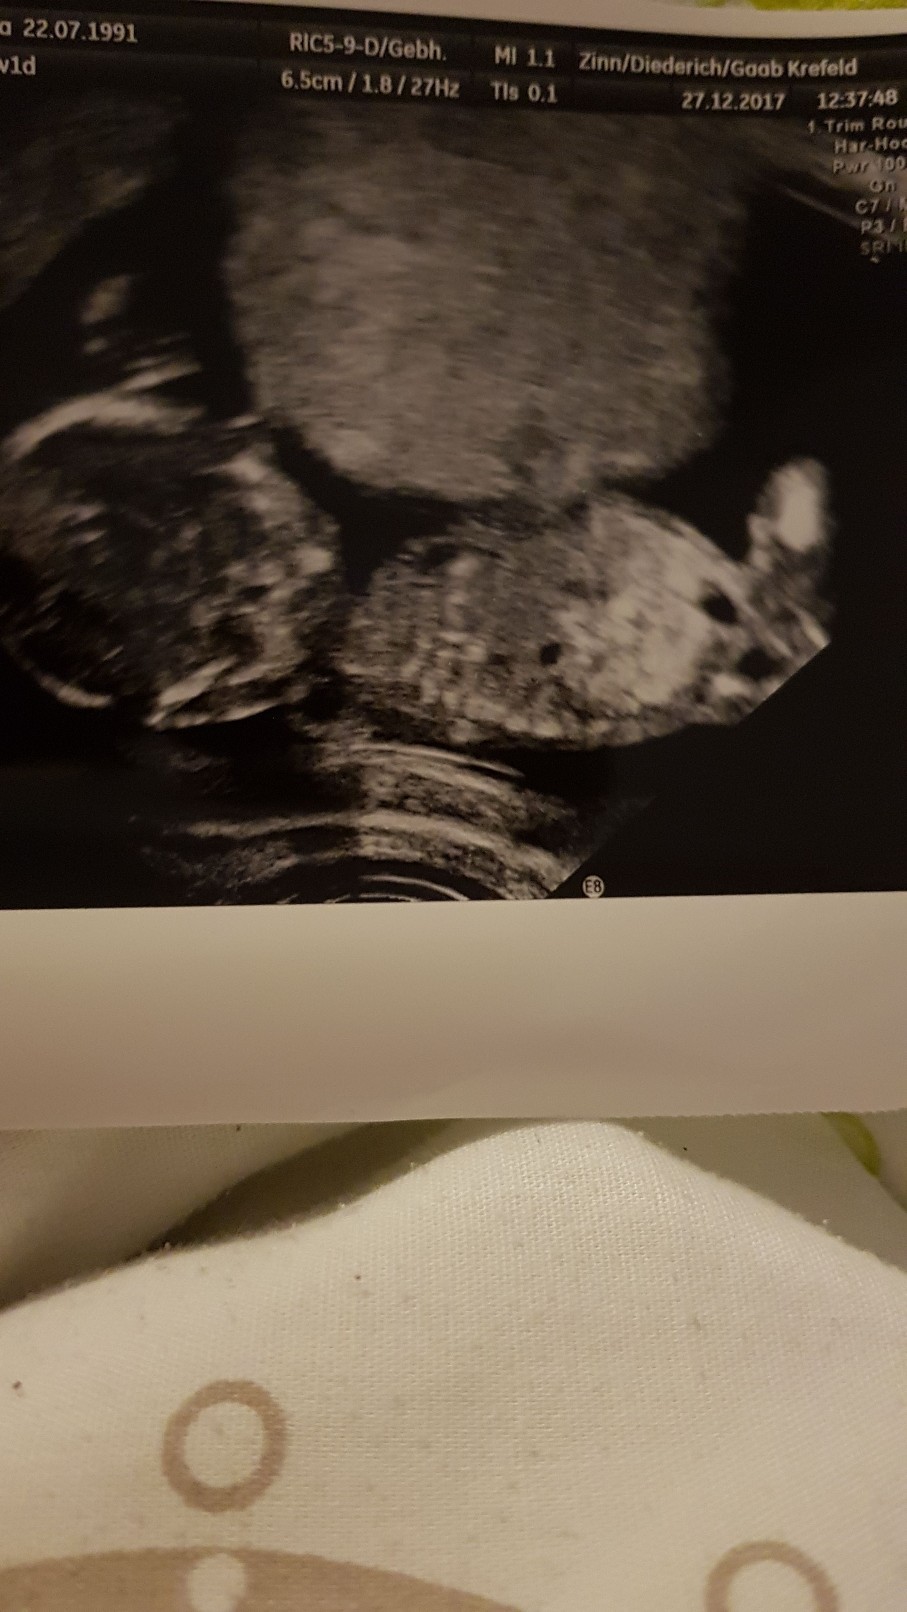

Moje z dzis[emoji6]